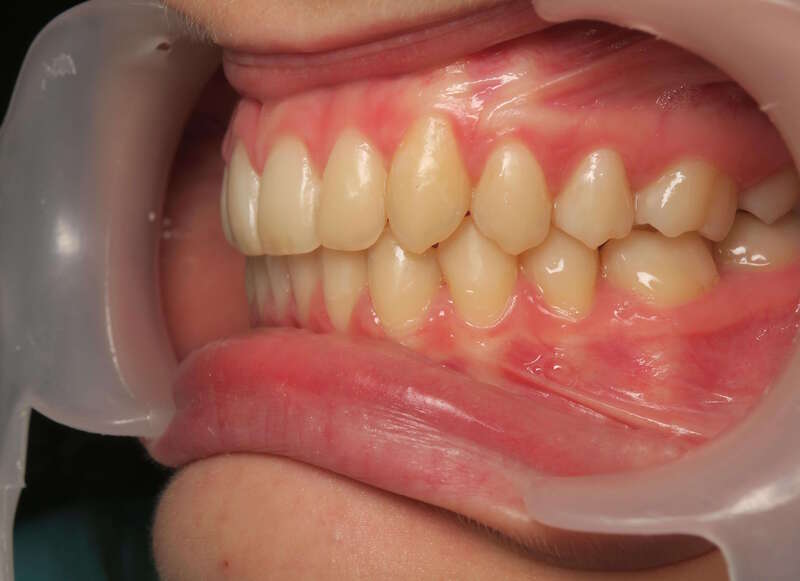

Cas n°1 traité par aligneurs - adolescent

Ce cas d’une adolescente illustre la correction d'une Classe II avec supraclusion par aligneurs. La stratégie thérapeutique a reposé sur une distalisation séquentielle de l'arcade supérieure. Ce mouvement précis a permis de reculer les dents maxillaires étape par étape pour annuler le surplomb (overjet) sans extractions.

• Correction fonctionnelle : Retour à un engrènement de Classe I stable et correction du recouvrement vertical.

• Esthétique restaurée : Harmonisation globale du sourire et du profil.

• Approche moderne : Un traitement discret, confortable et hautement prévisible.

Le résultat final montre une occlusion saine et un sourire parfaitement aligné, garantissant une santé dentaire et articulaire optimale pour l'avenir.